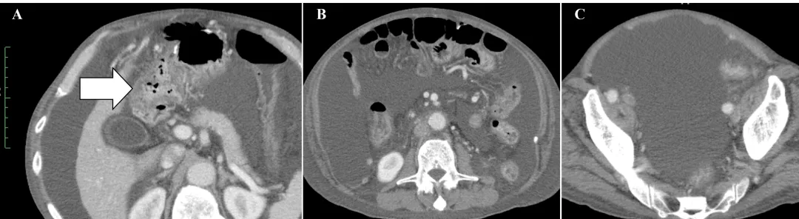

案例2:难治性宫颈癌转移灶消失,免疫功能恢复